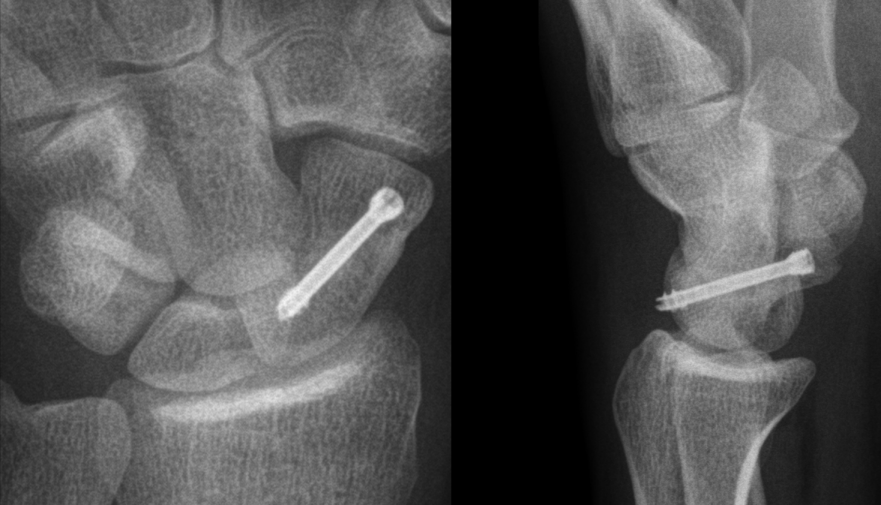

The mean time between trauma and surgery was 10 days. Two cases were treated with an antegrade whereas nineteen with a retrograde approach. For the both methods, a longitudinal incision less than 1 cm was required and reduction aided through the use of a fluoroscope. After blunt dissection was performed to the level of the scaphoid, a guide wire was carefully inserted under fluoroscopic control. The screw length was measured and a cannulated reamer was inserted over the wire. The drilling did not proceed beyond the cortex of the proximal scaphoid pole. The reamer was then removed and a 3.0 mm diameter HCS screw of the appropriate length was inserted. The screw head was still locked by the compression sleeve. When the compression sleeve contacted the proximal pole, the distal thread of the screw engaged the proximal scaphoid fragment and compressed the proximal and distal fragments. The compression sleeve was then retracted and the head of the screw securely seated. The screw position was verified through fluoroscopic methods (Figure 1 [Fig. 1]). A short-arm thumb-spica cast was applied postoperatively allowing unrestricted thumb interphalangeal motion while maintaining the wrist in slight extension. Cast immobilisation was discontinued after 14 days and converted to a removeable splint. Active range-of-motion exercises were encouraged at 6 weeks. Full weight-bearing was allowed after 12 weeks.

Figure 1: A.p. and lateral radiographs after insertion of the Headless Compression Screw